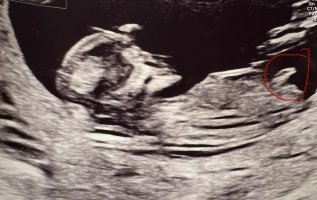

Osaako joku arvioida meidän kuvasta? Kätilö sanoi, että tuo ympyröity olisi napanupra, eikä siitä voi päätellä mitään. Facebookin nub-teoria ryhmässä sanottin, että se olisi nub?!

Rv 12+3.